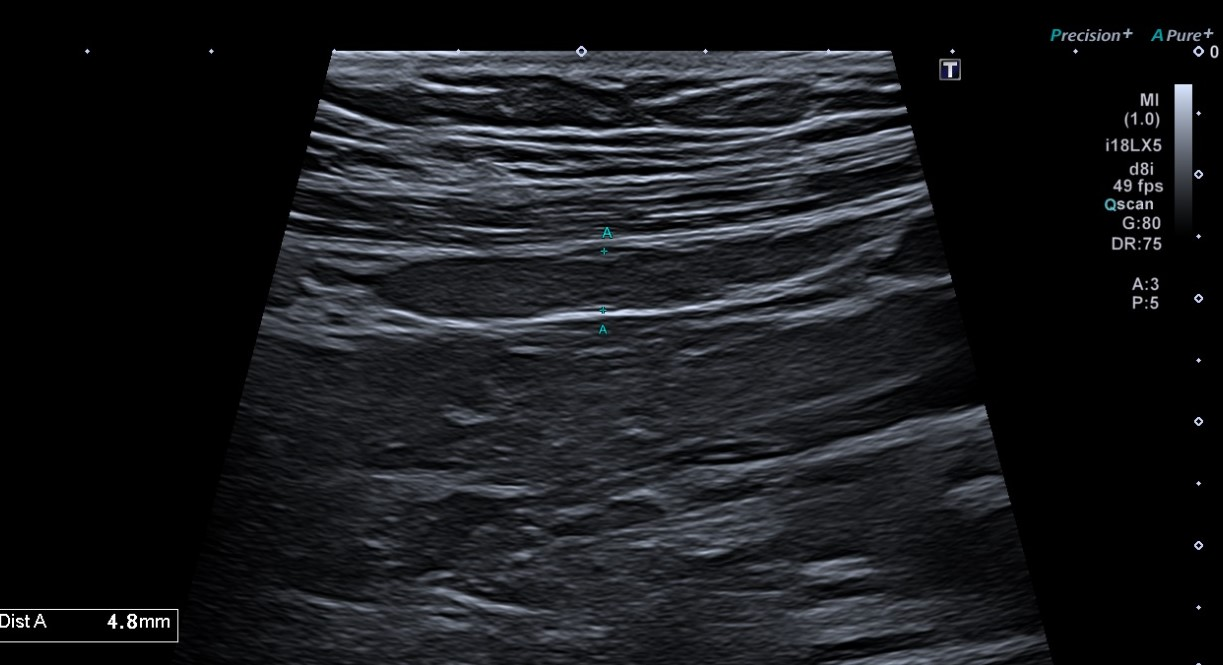

Ecografía partes blandas: En localización infraumbilical, sin aparente dependencia de estructuras profundas ni modificación en maniobra de Valsalva, lesión hipoecoica bilobulada (4,3 x 8,5 x 7,1 mm) con aparente conexión hacia región vesical, sobre la que no se demuestra vascularización, inespecífica, que podría corresponder a seno uracal, sin poder descartar sobreinfección asociada.